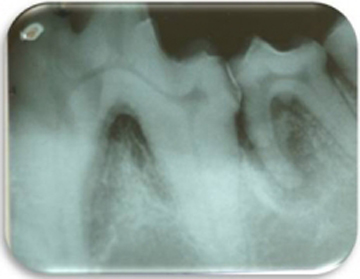

Los problemas que aquejan los tejidos periodontales son varios aunque su etiología primaria siempre es la misma, el alimento y las bacterias que se pegan a los dientes formando la placa dento bacteriana (PDB) y el sarro que destruyen lentamente pero de manera progresiva los tejidos de sostén dental. La enfermedad periodontal es la enfermedad de mayor incidencia y prevalencia en perros y gatos por lo que su diagnóstico, prevención y tratamiento es uno de los retos que el médico veterinario tiene en su trabajo clínico. La enfermedad periodontal es la causa más común de enfermedades como endocarditis bacteriana y artritis infecciosa por lo que el propietario y médico tratante deben de tener especial interés en la prevención y tratamiento de esta patología. La enfermedad periodontal se clasifica dependiendo de los tejidos afectados así como según el grado de destrucción del tejido óseo. Según el tejido afectado como “Gingivitis” cuando afecta la encía libre y papilar, y “Periodontitis” cuando ya afecta el tejido óseo y el ligamento periodontal formando destrucciones del hueso alveolar muy características de la enfermedad denominadas bolsas periodontales las cuales según la forma de destrucción pueden clasificarse como horizontales o verticales. La periodontitis se diagnóstica con una sonda periodontal que es un instrumento que tiene líneas de medición en su punta de trabajo y que se introduce en el surco gingival para medir en milímetros la destrucción ósea alveolar. Otro método de diagnóstico es la radiografía periapical en la cual se puede observar claramente el grado y forma de destrucción ósea alveolar.